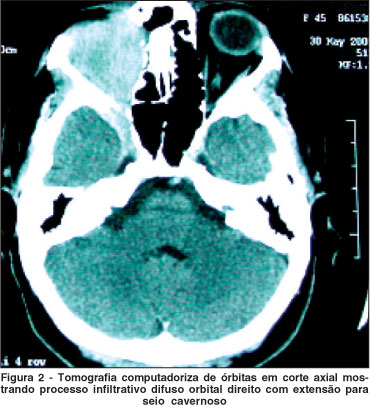

Nova avaliação foi feita em 4 semanas: o quadro doloroso e inflamatório orbital progrediu mesmo com a medicação em uso; optou-se assim pela realização de biópsia da órbita direita, que mostrou infiltrado inflamatório polimórfico com presença de linfócitos T e B, plasmócitos, histiócitos e eosinófilos confirmando o diagnóstico de IIO. Nova TC foi feita mostrando progressão do quadro infiltrativo com comprometimento das fissuras orbitais, seio cavernoso, fossas anterior e média do crânio e fossa pterigomaxilar direita (Figura 2). Haviam também erosões focais das paredes e rebordos orbitais.

IIO com extensão extra-orbital é bastante incomum(2,5). No presente estudo, o processo inflamatório inicialmente estava restrito à órbita e com a evolução do quadro, progrediu para seio cavernoso, fossa anterior e média do crânio e fossa pterigomaxilar. Alguns autores descreveram 2 casos de IIO tipo esclerosante com envolvimento da fossa infratemporal e pterigopalatina; um dos pacientes apresentou erosão óssea como o caso descrito neste estudo(5). A erosão óssea pode sugerir um processo tumoral maligno, dificultando assim o diagnóstico diferencial. Com o resultado da segunda TC mostrando infiltração difusa da órbita e extensão extra-orbital, realizamos nova biópsia, pois suspeitávamos de um processo neoplásico. Em outro estudo, dor orbital não estava presente em todos os casos e a realização dos exames de imagem, como a TC, foi fundamental para a determinação da extensão extra-orbital(6).